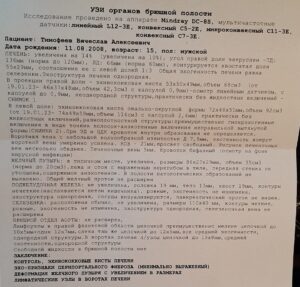

Фото УЗИ приложу, самое первое и на сегодняшний день.